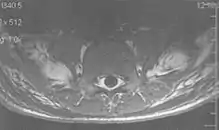

Metal artifacts occur at interfaces of tissues with different magnetic susceptibilities, which cause local magnetic fields to distort the external magnetic field. This distortion changes the precession frequency in the tissue leading to spatial mismapping of information. The degree of distortion depends on the type of metal (stainless steel having a greater distorting effect than titanium alloy), the type of interface (most striking effect at soft tissue-metal interfaces), pulse sequence and imaging parameters. Metal artifacts are caused by external ferromagnetics such as cobalt containing make-up, internal ferromagnetics such as surgical clips, spinal hardware and other orthopaedic devices, and in some cases, metallic objects swallowed by people with pica.[3] Manifestation of these artifacts is variable, including total signal loss, peripheral high signal and image distortion (Figs 3 and 4).[1] Reduction of these artifacts can be attempted by orientating the long axis of an implant or device parallel to the long axis of the external magnetic field, possible with mobile extremity imaging and an open magnet. Further methods used are choosing the appropriate frequency encoding direction, since metal artifacts are most pronounced in this direction, using smaller voxel sizes, fast imaging sequences, increased readout bandwidth and avoiding gradient-echo imaging when metal is present. A technique called MARS (metal artifact reduction sequence) applies an additional gradient, along the slice select gradient at the time the frequency encoding gradient is applied. ==Signal processing dependent artifacts== The ways in which the data are sampled, processed and mapped out on the image matrix manifest these artifacts.[1]